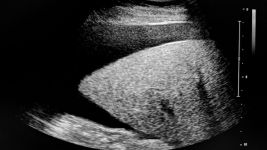

Sve što treba da znate o cistama na bubrezima

Ciste na bubrezima

Ciste na bubrezima su tečno ispunjeni mehurići, obično benigne. Simptomi uključuju bol i hematuriju. Dijagnoza se postavlja testovima snimanja, a...